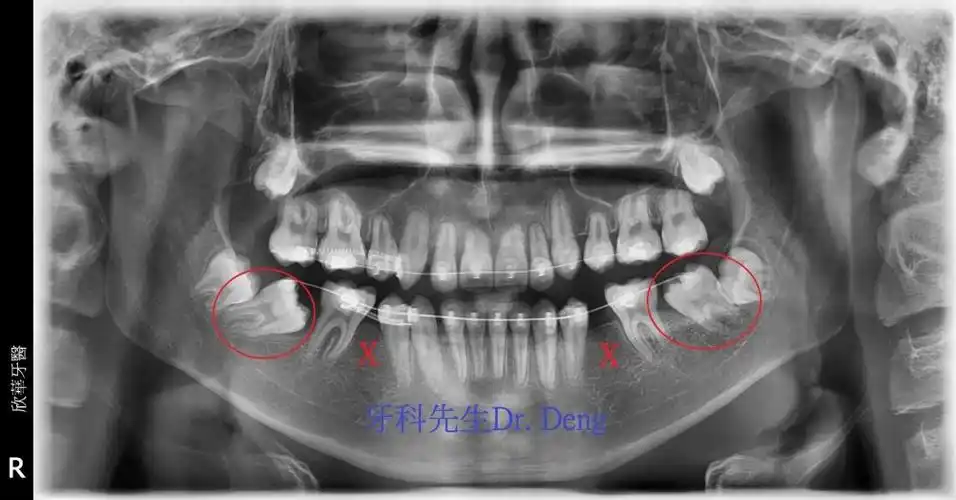

first premolar transposition(双侧上颚犬齿与第一小臼齿异位)

拔除下颚两侧第二小臼齿后把第一与第二大臼齿往前提供倾斜大臼齿转正

右上及左上拔除第一小臼齿,将上颚前牙向内移动,以减少外凸的情形.

安氏二类错合,伴前牙深咬,下颚牙弓狭窄,与上颚右侧第一小臼齿与犬齿